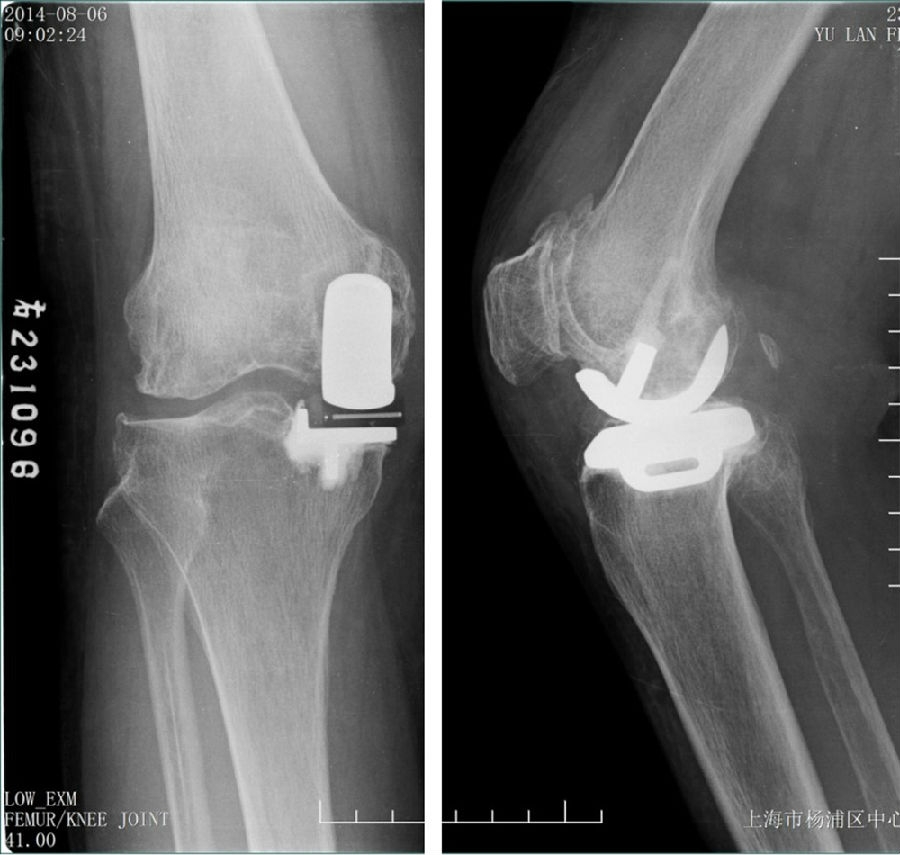

Case2:二期Bi-UKA治疗进展性OA

术前影像

术后5年,外侧进展性OA

LUKA治疗外侧进展性OA